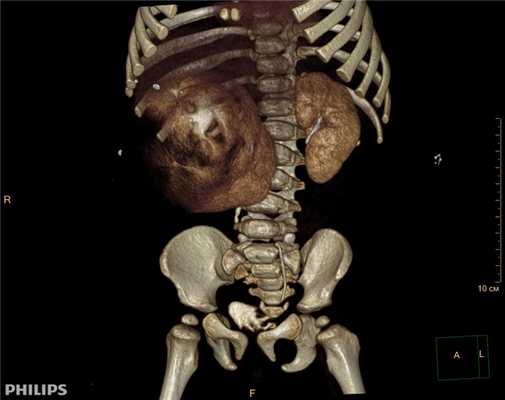

3D-реконструкции опухоли Вильмса пациентов детского отделения НМИЦ онкологии им. Н.Н. Петрова

Опухоль Вильмса. Компьютерная томография

Рисунок 1. КТ брюшной полости ребенка с большой нефробластомой с метастазами в печень.

Клинически: при пальпации опухоль в проекции правой почки до 12 см в диаметре. Общеклинические исследования в пределах возрастной нормы. При КТ органов брюшной и грудной полости: КТ-картина объемного образования правой почки без признаков интрапульмональных метастазов (см. рис. 2). УЗИ брюшной полости: в проекции правой почки солидно-кистозное образование 101ґ114ґ99 мм, объемом 500 мл, васкуляризация активная, интактная часть почки 57ґ12ґ40 мм. Объемное образование правой почки — опухоль Вильмса. Предварительный диагноз: опухоль Вильмса правой почки, 2-я стадия.

Ребенку проведена предоперационная химиотерапия. На 5-й неделе лечения КТ-контроль показал уменьшение опухоли в размерах до 90ґ80ґ100 мм (см. рис. 3).